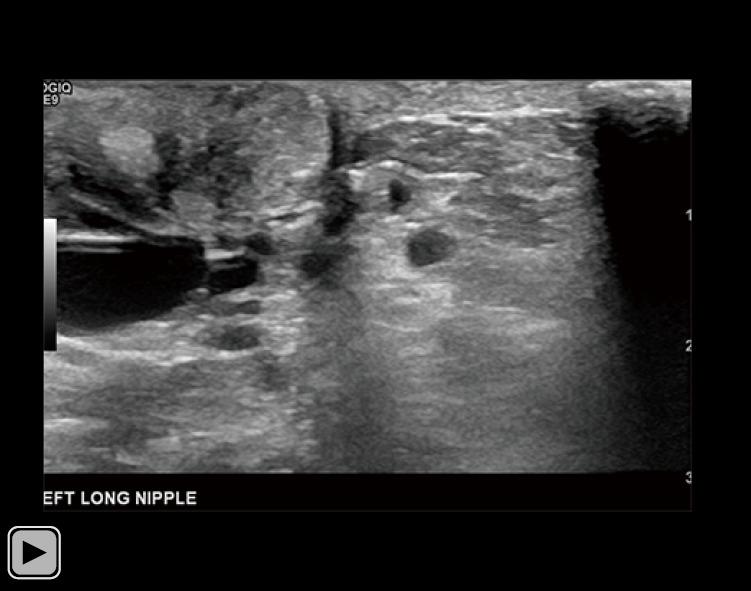

A 34-year-old lactating female presented with a 3-month history of worsening left breast and nipple pain radiating to the left upper outer quadrant, not relieved with conservative therapies. The physical exam revealed a small indentation and a small palpable nodule of the left nipple. There was no associated erythema or redness. Targeted ultrasound and subareolar magnification views revealed findings most consistent with a probably benign inspissated clogged milk duct. Given the patient's history, inability to express milk from the left breast, and plan to lactate for another year, ultrasound-guided aspiration was desired. Post-aspiration images demonstrated complete resolution of the nipple mass. Pathology revealed blood and proteinaceous material, in keeping with the diagnosis of inspissated clogged milk duct. Following the procedure, the patient's symptoms resolved completely.

一名34岁的哺乳期女性,左乳房和乳头疼痛加剧3个月,疼痛放射至左乳房外上象限,保守治疗未能缓解。体格检查发现左乳头有一个小凹陷和一个可触及的小结节。无相关红斑或发红。针对性超声检查和乳晕下放大视图显示的结果最符合可能为良性的浓缩性乳腺管堵塞。鉴于患者的病史、左乳房无法挤出乳汁以及计划再哺乳一年,希望进行超声引导下抽吸。抽吸后的图像显示乳头肿块完全消失。病理检查显示为血液和蛋白质物质,符合浓缩性乳腺管堵塞的诊断。手术后,患者症状完全缓解。